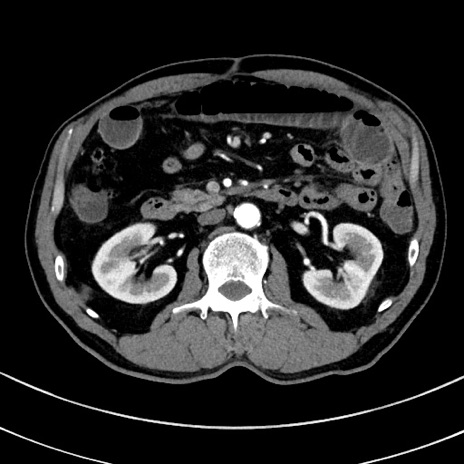

症例8(横断像)

【症例】 60歳代男性

【主訴】 黒色吐物

【現病歴】 4日前から嘔気自覚、2日前の朝食後にも嘔気あり、自分で手で嘔吐反射起こし嘔吐したところ血が混ざっていたため受診。

【既往歴】 5年前汎発性腹膜炎を伴う急性虫垂炎で手術、高血圧、前立腺肥大症、高脂血症

【身体所見】 腹部正中に手術癩痕あり 腹部平坦・軟圧痛なし膨満感あり

【データ】WBC 8400、CRP 4.54